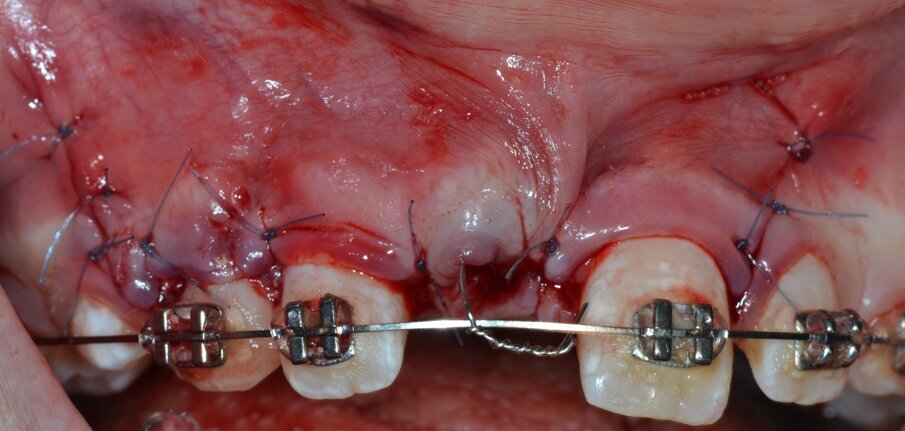

Si procede all’esecuzione dell’alveolectomia conduttrice (Figg. 14, 15) allo scopo di facilitare la trazione ortodontica mediante inserto dedicato montato su dispositivo piezoelettrico (ES009ST Esacrom Srl, Imola, Italia) e, successivamente, all’adesione del bracket ortodontico sulla corona dell’elemento 1.1 (Figg. 16, 17). L’ ultimo tempo operatorio prevede il riposizionamento e la sutura del lembo (Fig. 18) con punti staccati in Nylon 5/04 seguito dal riposizionamento in sede del filo ortodontico (Fig. 19).

Fig. 18_Riposizionamento del lembo e sutura con filo in Nylon 5/0.

Fig. 19_Riposizionamento del filo ortodontico.